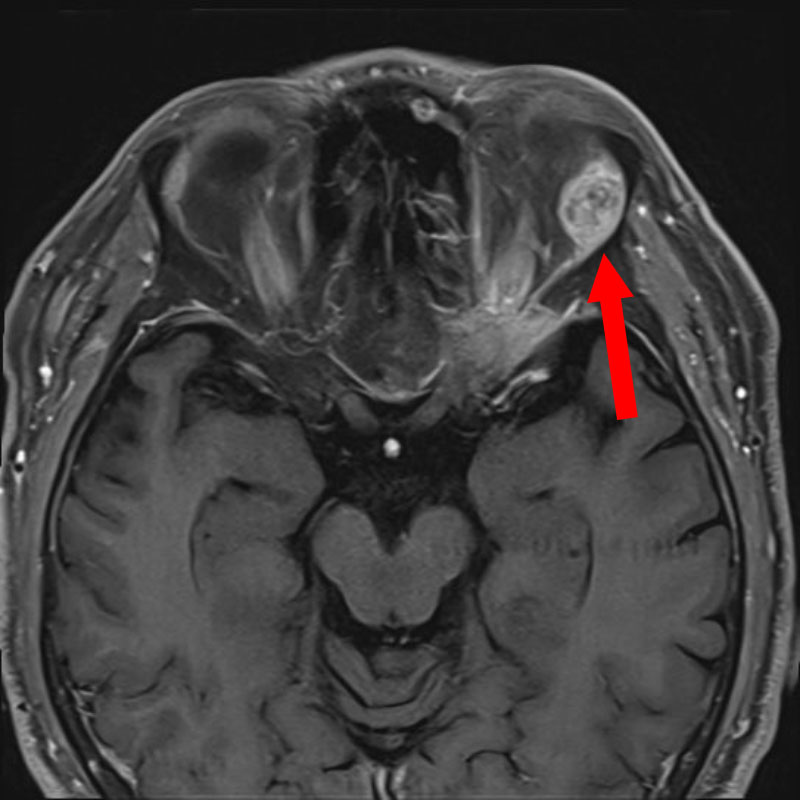

症例 '25年11月

No.

696

※ 画像をクリックすると拡大表示します。症例No.は平成29年から起算しています。

年_番号

手術年月

患者年齢

’25_98

'25年11月

70代

病名

術式

備考

眼窩腫瘍

頭蓋内腫瘍摘出術

断層撮影

手術前

1

手術前2